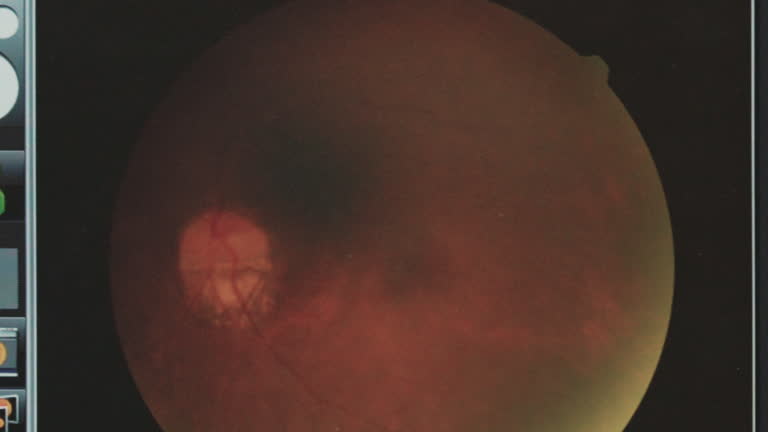

Browse 33 ²¹³Ü³Ù³ó±ð²Ô³Ù¾±³¦Ìýdiabetic retinopathy stock videos, stock footage, and video clips available in a variety of formats and sizes to fit your needs, or explore diabetic retinopathy screeningÌý´Ç°ùÌýproliferative diabetic retinopathy stock videos to discover the perfect clip for your project.